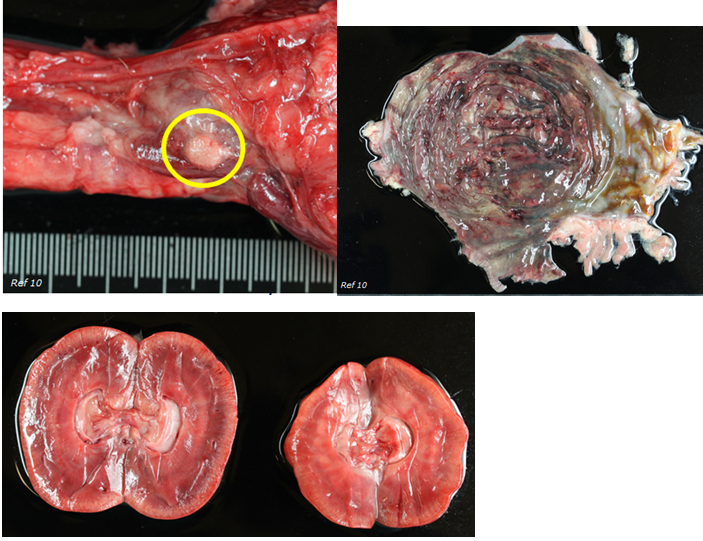

Sudden death due to gastric dilation and volvulus (GDV). On post-mortem examination, the urinary tract appeared grossly abnormal.

What is your diagnosis?

Urinary bladder in pic

Diagnosis (urinary bladder):

Moderate to severe diffuse chronic follicular cystitis

(incidental finding)